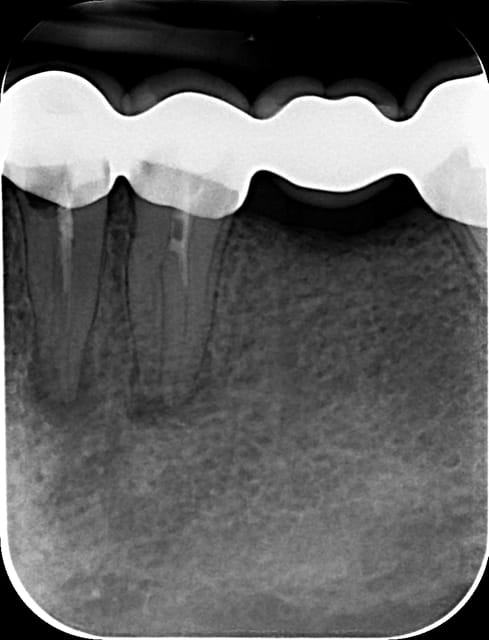

Bonjour a tout !

Initial e après obturation